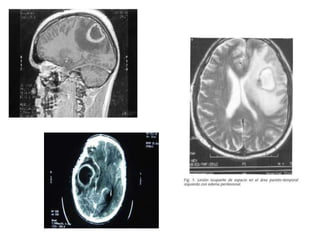

La introducción de la TAC y la RNM ha revolucionado el

diagnóstico, determinando el tamaño, localización y fase

evolutiva (fase de cerebritis o de absceso encapsulado), permite

planificar las opciones de tratamiento, y hace posible los

estudios de seguimiento por imagen

En la TAC es el de una lesión hipodensa rodeada de un anillo

realzado tras la administración de contraste puede dar también

información adicional como la extensión del edema que rodea al

absceso, la presencia de hidrocefalia o desplazamiento de linea

media.

• La RNM parece más sensible que la TAC en la fase de cerebritis, así

como en la detección del edema cerebral asociado y de la

extensión extraparenquimatosa de un absceso.